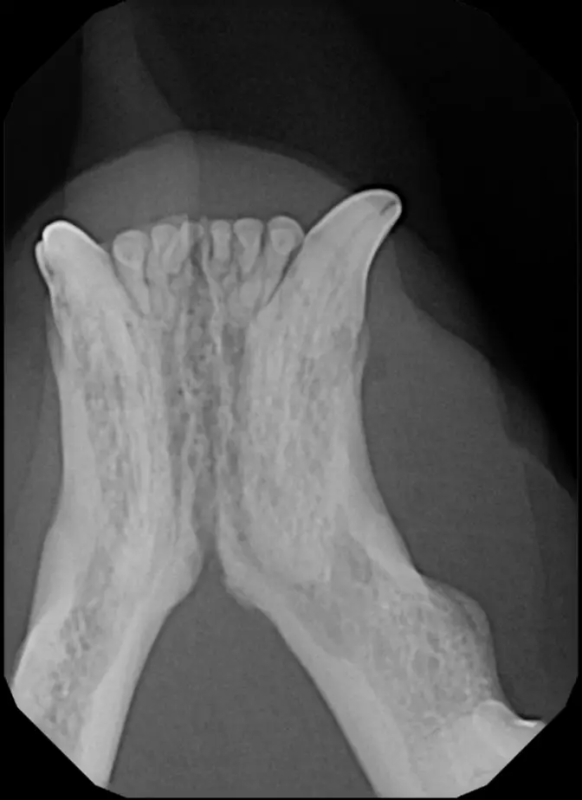

Root canal therapy is an excellent option for saving important teeth that have been fractured or are determined to be non-vital. The procedure is performed exactly as it would be for a human, except your pet will be dreaming peacefully under anesthesia. In many cases, root canal therapy is much easier on your pet than extraction, and preserves the structure of the tooth. It is important to have the root canal x-rayed periodically to monitor for any problems.

Periodontal disease is extremely common in dogs and cats. Over 80% of dogs and cats over two years of age have some degree of periodontal disease. Periodontal disease is best prevented by yearly professional dental cleanings starting at two years of age and at home brushing at least three times weekly. Brushing should begin at a very early age to allow your new pet to get used to regular brushing. In severe cases of infection or periodontal disease, the teeth may need to be surgically extracted. Extractions should always involve x-rays of the tooth first, as many teeth have multiple roots or may be diseased below where the eye can see. Extracting larger teeth in animals requires oral surgery, equivalent to removing wisdom teeth in people. It is vital that all of the tooth and roots be removed for the periodontal infection to resolve. In cases of important teeth with mild to moderate periodontal disease, multiple periodontal treatments can be offered to help save these teeth.

The Center now provides advanced imaging via cone beam CT. Cone beam CT is excellent for visualization of bony structures of the skull, nasal cavity, teeth, and ears. Cone beam CT is especially helpful for diagnosing dental disease and evaluation of jaw fractures. It can also be useful for evaluating the sinuses and tympanic bulla. Cone beam CT can be used in conjunction with nasal biopsy and culture to evaluate nasal discharge whether chronic or acute.